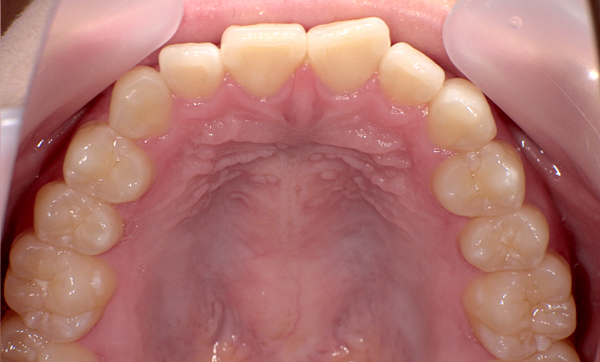

症例_008 「上下の前歯」症例

治療期間:13ヶ月金額:57万円+税40代女性捻転歯前歯のガタガタ

Before | After |